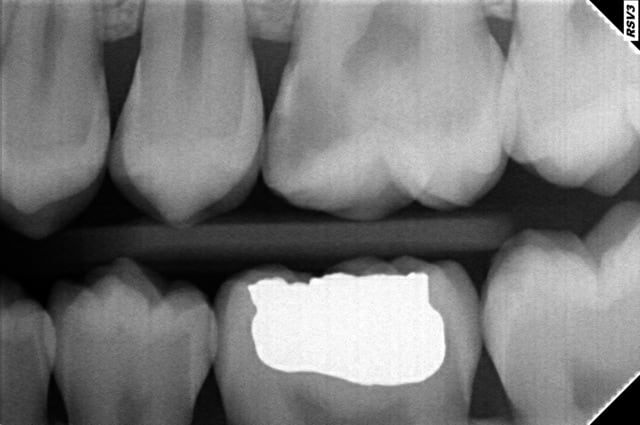

Patiente de 21 ans arrive avec une hyperémie de la 26. je pose de la biodentine et je lui fait un devis pour un inlay (à 235 euros). Je viens de me mettre aux inlays et au concept de garder la dent vivante (j'ai fait la journée de formation avec cingulum à clinic all).

On avait perdu une partie de la cuspide mv et de la mp et un inlay était indiqué je pense.

quel interet pour un patient, d'avoir a choisir entre un onlay a 250 300 euros, "couleur des dents", structure proche de la dentine et un composite a 40 euros, couleurs des dents, structure proche de la dentine.

deja oublie les composites, en france si tu es conventionné et propose onlay ou plombage.

Rien que le point de contact n'a rien à voir en général, et ça fait déjà une gigantesque différence.

Si tu as un bon système de matriçage ( genre palodent + ) pour des cavités type inlay, tu as un super point de contact avec un compo "classique", les bons arguments seraient plutôt dans le matériau si tu fais des inlay ceram ou mixte ( Lava ultimate par ex ), ainsi que dans la réduction d'infiltration puisque monobloc... non ?

On peut avoir un bon point de contact avec un simple composite dans beaucoup de cas, mais soyons réalistes, quel pourcentage des praticiens en France mettent en oeuvre les moyens nécessaires pour avoir ce point de contact de qualité ?